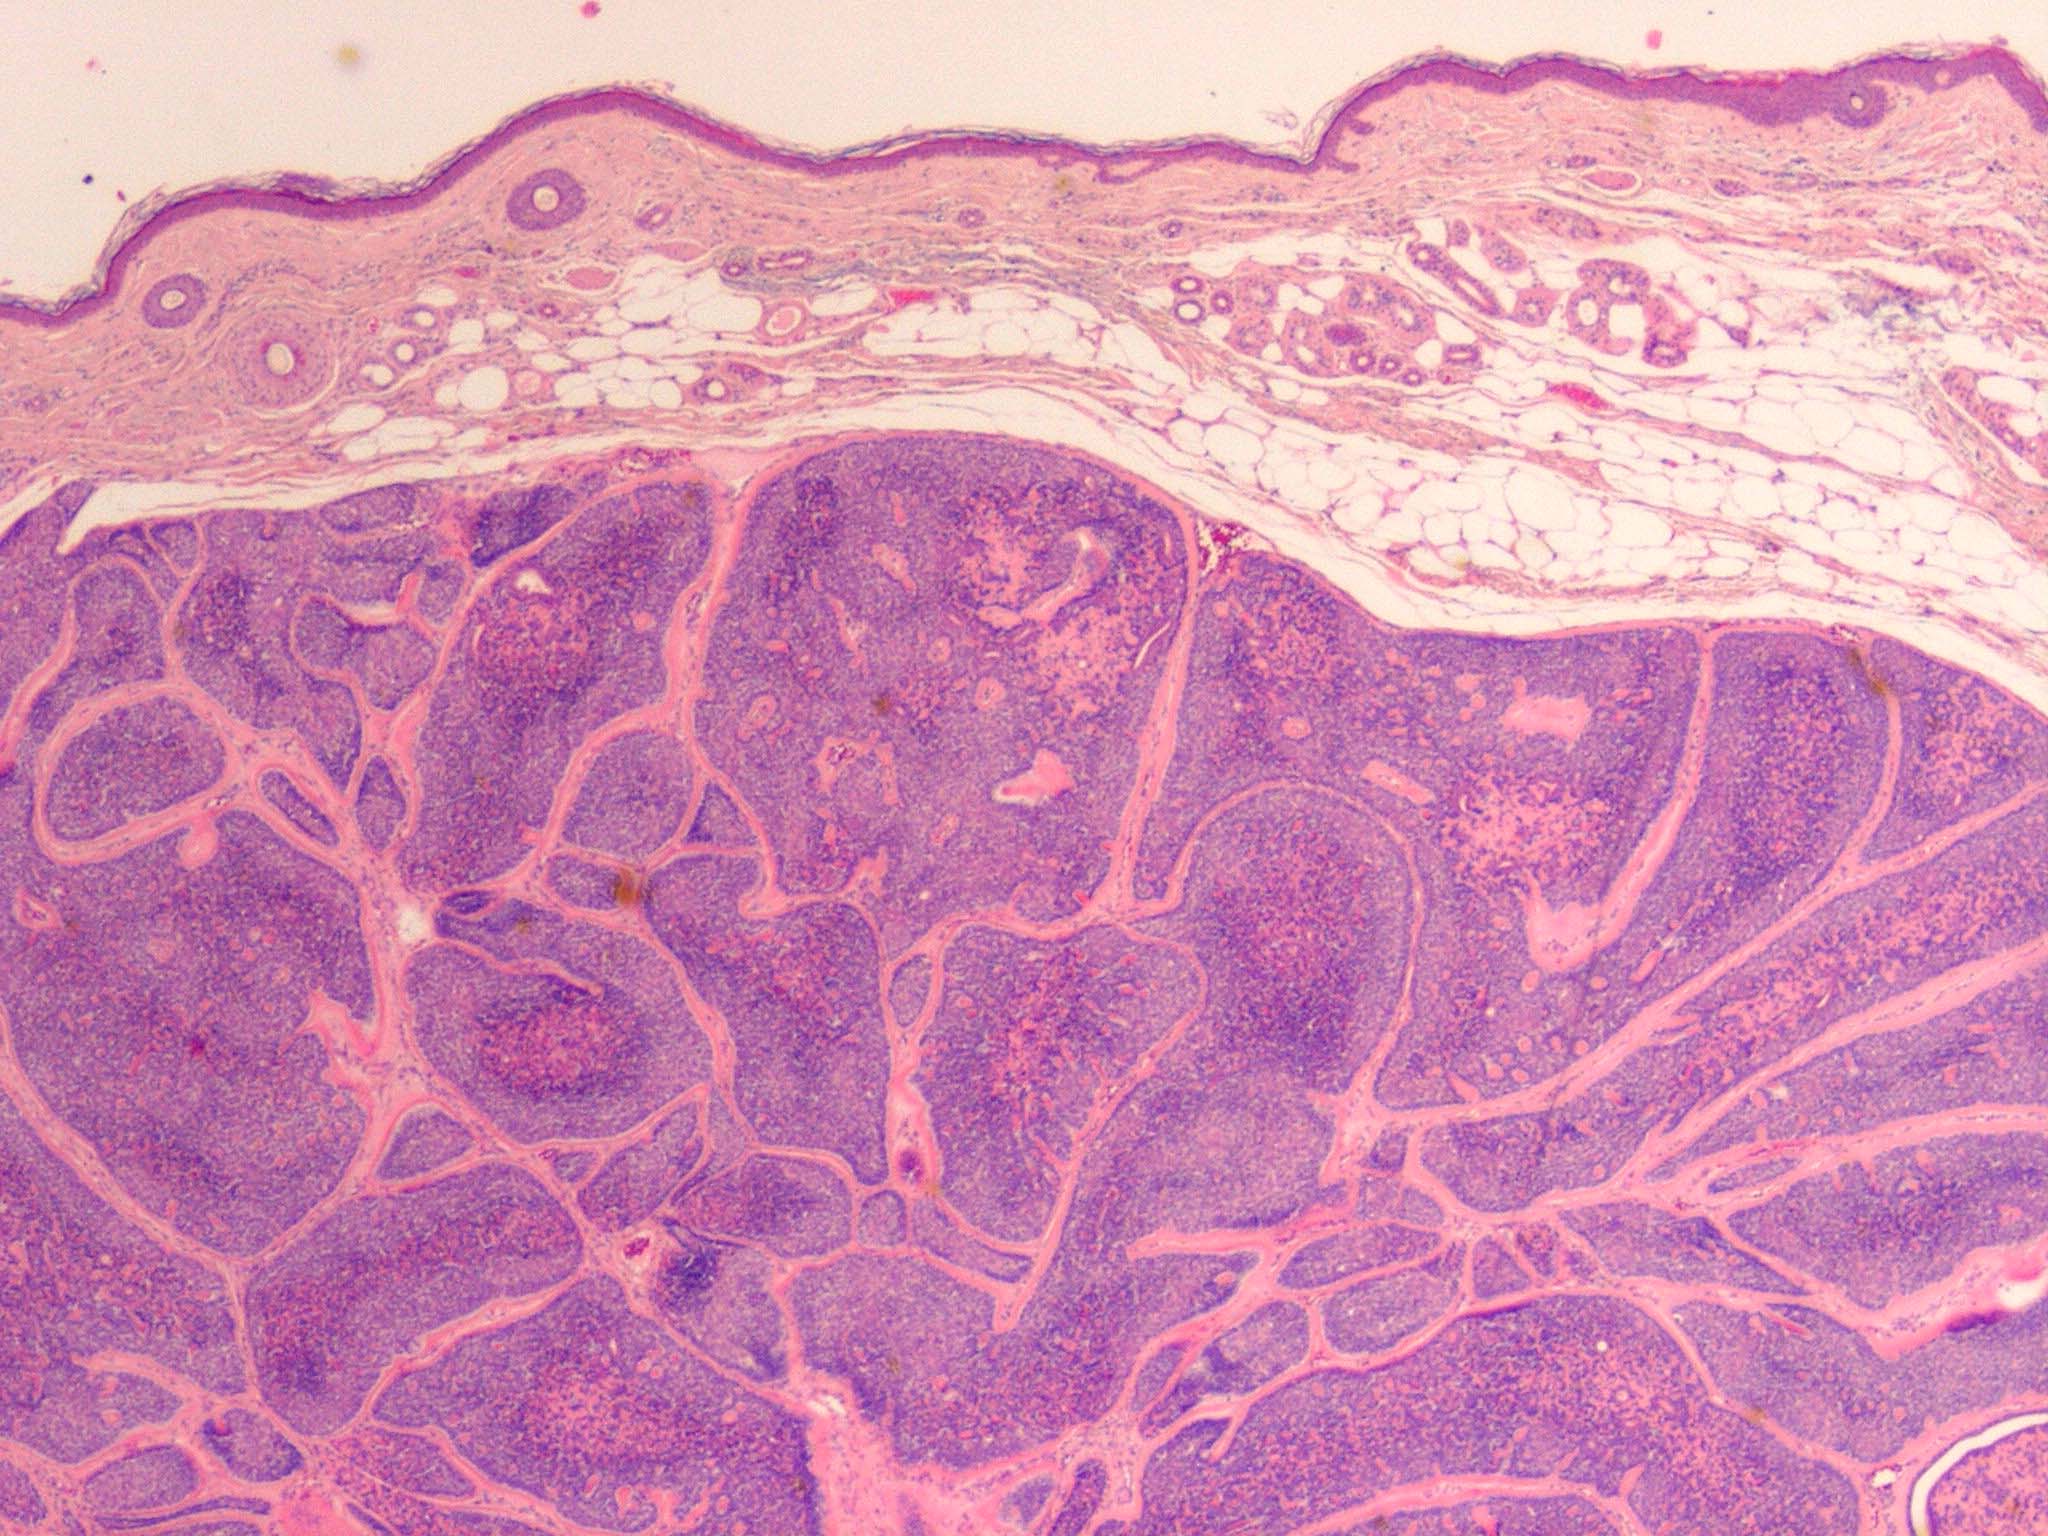

Cylindroma =الأسطوانوم

OLYMPUS DIGITAL CAMERA